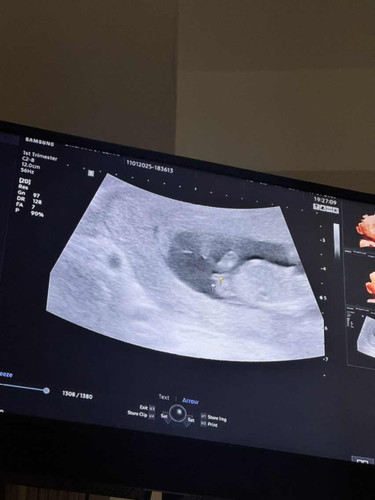

แม่ๆช่วยดูเพศหน่อยค่ะ

หมอบอกว่าอาจจะได้ลูกชาย แต่สามีอยากให้ลูกเป็นลูกสาว5555 แม่ๆรุ่นพี่ช่วยทายเพศหน่อยนะคะะ 💓💓 #ลูกคนแรก #ช่วยบอกกันหน่อยนะคะ

บ้านนี้ชายมีจู๋เล็กๆโด่เลยค่ะ 15 w

ถ้าผู้หญิงจะเป็นแบบนี้ค่ะแม่

น่าจะผชนะคะ ผญจะประมาณนี้ค่ะ

น่าจะชายนะคะ

แบบนี้ชายชัวค่ะแม่

น้องมีงวงค่ะแม่🥰

คิดว่าผู้ชายค่ะแม่

ในรูปซาวด์ตอน 11-12 วีคค่ะแม่